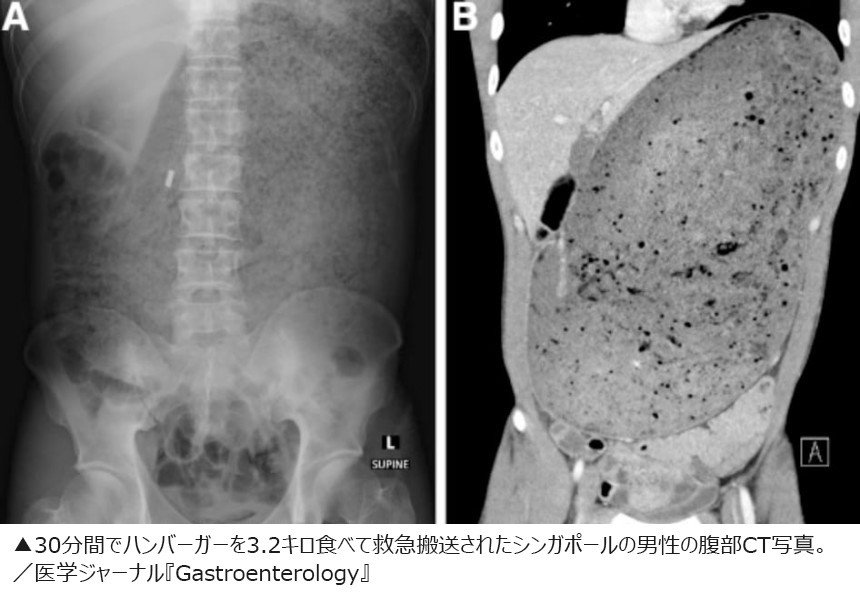

【写真】30分間でハンバーガーを3.2キロ食べて救急搬送された男性の腹部CT写真

CT撮影の結果、男性の胃と十二指腸は摂取した飲食物で膨らんで巨大になっていた。さらに、消化されていない食べ物が周辺の臓器を圧迫し、すい臓が砕けていた。

公開された男性の腹部CT写真には、へそのすぐ上から肩の近くまで飲食物でパンパンになっている様子がはっきりと写っている。男性は入院し、膨張した胃の圧力を下げるためにカテーテルによる胃の洗浄を受けたが、それでも症状は改善しなかった。